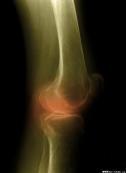

• 增生性骨關(guān)節(jié)病

臨床上多見的增生性骨關(guān)節(jié)病可有多個名稱,包括退化性關(guān)節(jié)炎、骨關(guān)節(jié)炎及肥大性關(guān)節(jié)炎等。本病是由于關(guān)節(jié)退行性變,以致關(guān)節(jié)軟骨被破壞而引起的慢性關(guān)節(jié)病。...

• 大骨節(jié)病

大骨節(jié)病是指一種地方性、變形性骨關(guān)節(jié)病,國內(nèi)又叫矮人病、算盤珠病等,國際醫(yī)學界稱為Kaschin-Beck病。大骨節(jié)病在國外主要分布于西伯利亞東部和朝鮮北部,在我國分布范圍...